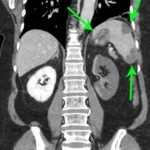

On the coronal sections of computed tomography (CT), bilateral renal infarctions (blue arrows) and several splenic infarctions (green arrows) are noted. Of particular interest, part of the clot totally occluding the left renal artery visibly extends into the aorta (red arrow). The vascular reconstruction image is remarkable for the absent left kidney, the unusual contour of the right kidney and the abnormal splenic blush.

Classic emergency medicine teaching dictates that when a patient with atrial fibrillation has abdominal pain “out of proportion” to the examination, one must consider mesenteric ischemia. Although the bowels clearly carry the highest embolic risk for abdominal viscera, other organs are at risk as well. This case illustrates a rare constellation of segmental splenic infarcts and bilateral renal infarction, with complete left renal artery occlusion stemming from multiple emboli.